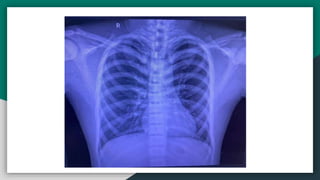

Respiratory Exam

● Inspection: No chest wall deformities,

visible scars or pulsations. Symmetrical

chest movement, thoracoabdominal

breathing, no signs of distress,

RR=19/min.

● Palpation: No tracheal deviation, Apex

beat localized in 5th Intercostal space

midclavicular line.

● Percussion: Both lung fields resonant

on percussion.

● Auscultation: B/L normal vesicular

breathing